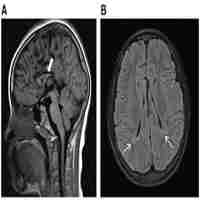

| Abstract | Background Mucopolysaccharidosis type VI (MPS VI) is a rare autosomal recessive inherited disease caused by mutations in the arylsulfatase B (ARSB) gene. MPS VI is a multisystemic disease resulting from a deficiency in arylsulfatase B causing an accumulation of glycosaminoglycans in the tissues and organs of the body. In this report, we present the case of a 16-year-old Chinese male who presented with vision loss caused by corneal opacity. MPS VI was confirmed by genetic diagnosis. Case presentation A 16-year-old Chinese male presented with a one-year history of binocular vision loss. The best-corrected visual acuity was 0.25 in the right eye and 0.5 in the left eye. Although slit-lamp examination revealed corneal opacification in both eyes, the ocular examinations of his parents were normal. At the same time, the patient presented with kyphotic deformity, short stature, joint and skeletal malformation, thick lips, long fingers, and coarse facial features. Genetic assessments revealed that ARSB was the causative gene. Compound heterozygous missense mutations were found in the ARSB gene, namely c.1325G > A (p. Thr442Met) (M1) and c.1197G > C (p. Phe399Leu) (M2). Genetic diagnosis confirmed that the patient had MPS VI. Conclusions This paper reports a case of MPS VI confirmed by genetic diagnosis. MPS VI is a multisystem metabolic disease, with corneal opacity as a concomitant ocular symptom. As it is difficult for ophthalmologists to definitively diagnose MPS VI, genetic testing is useful for disease confirmation. |